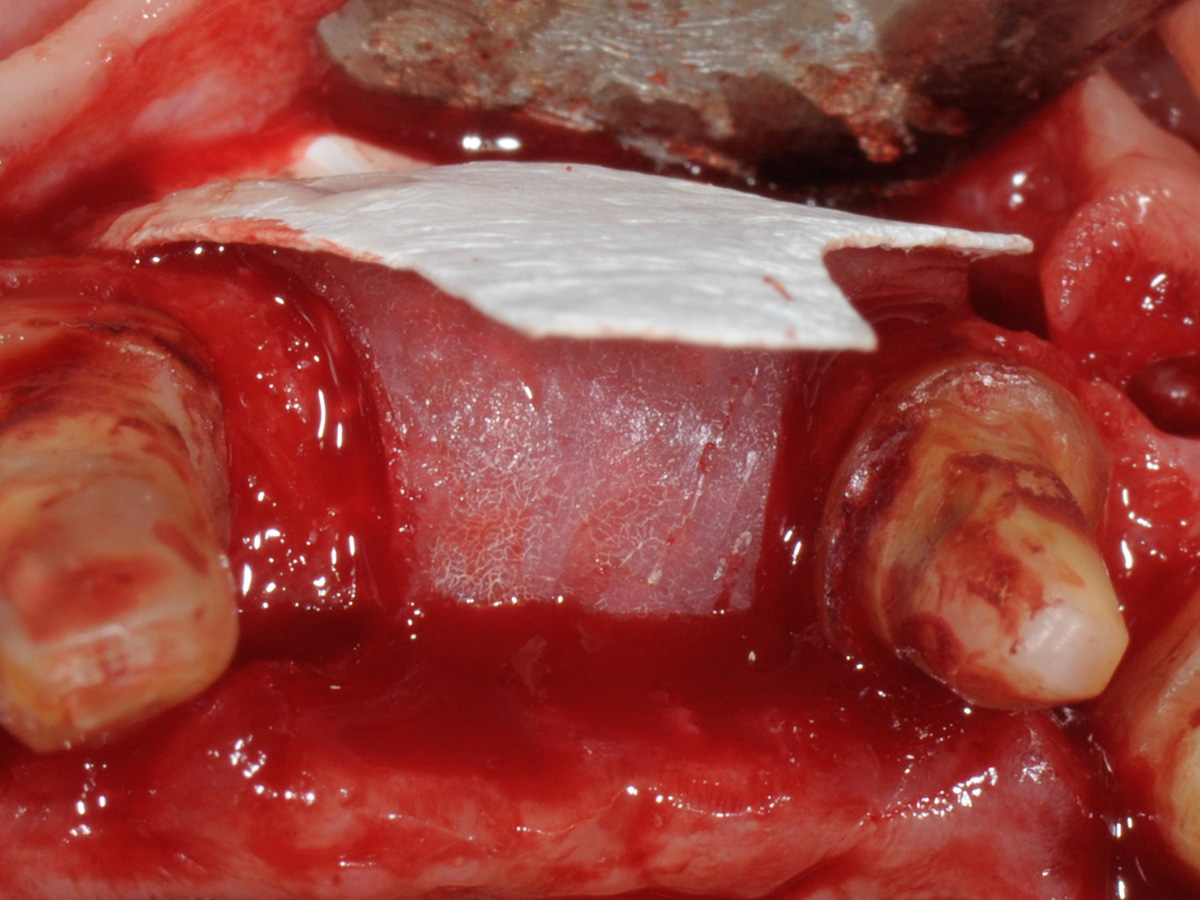

Abbildung 8

Aufbau mit OsteoBiol® mp3, Bone Lamina Soft und Evolution.